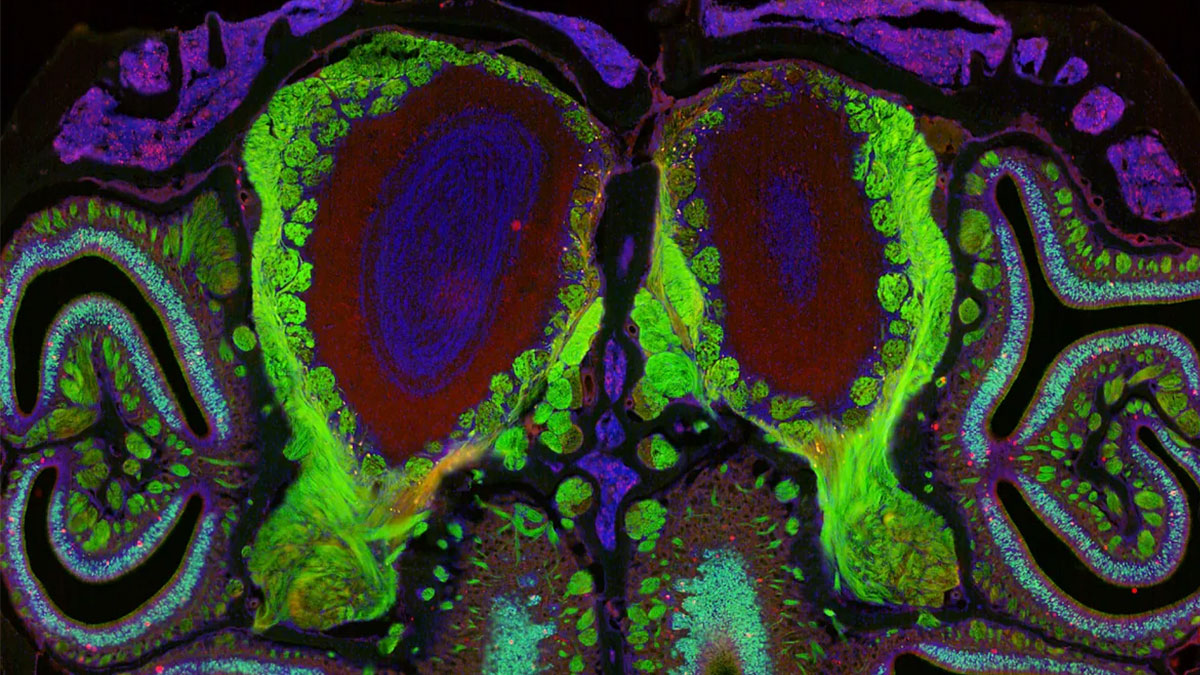

Harvard crea el primer mapa del olfato de la historia

Harvard marca un nuevo hito científico con la creación de este mapa en torno a los receptores olfativos de la nariz.

La ciencia avanza y construye nuevas realidades desde el laboratorio de Harvard. Allí un equipo de científicos ha logrado creado el primer mapa detallado de la organización de los receptores olfativos de la nariz, clave para futuras terapias para la pérdida del sentido.

En base al estudio publicado por la revista Cell, el atlas vislumbra cómo las neuronas expresan estos receptores olfativos, organizados en bandas horizontales según el tipo de receptor. El equipo también descubrió otro gran hallazgo en torno a este sentido «desconocido» para muchos: cómo este mapa de receptores coincide con los mapas de olor en el bulbo olfativo del cerebro; trazando la ruta de cómo la información fluye de la nariz al cerebro.

El mapa presenta cómo los más de 1.000 receptores que nos permiten oler se estructuran en la nariz, conformando un atlas esencial que recoge data sobre el entorno, cómo influye en las emociones o mejora el sentido del gusto. Y es que, el sentido del olfato era el único que no tenía mapa hasta el momento, debido a su complejidad.

Para dibujarlo, el equipo de investigadores se adentró en el universo microscópico de la nariz. Gracias a técnicas avanzadas de secuenciación celular, analizaron más de cinco millones de neuronas procedentes de más de 300 ratones, identificando qué receptores de olor expresa cada una y en qué punto exacto se ubican.

El siguiente paso fue descifrar cómo se organiza el sistema. La clave estaba en el ácido retinoico, una molécula capaz de regular la actividad genética. Los científicos observaron que su presencia introduce un gradiente dentro de la nariz que guía a cada neurona para activar el receptor adecuado según su posición. Alterar ese equilibrio -añadiendo o reduciendo ácido retinoico- desplaza el mapa olfativo, como si se movieran las coordenadas de un territorio sensorial.

Este hallazgo abre la puerta a estrategias futuras para tratar la pérdida del olfato, desde terapias con células madre hasta interfaces cerebro-computadora. Un campo con implicaciones que revela cómo perder el olfato también puede afectar al estado de ánimo e incluso aumentar el riesgo de depresión.